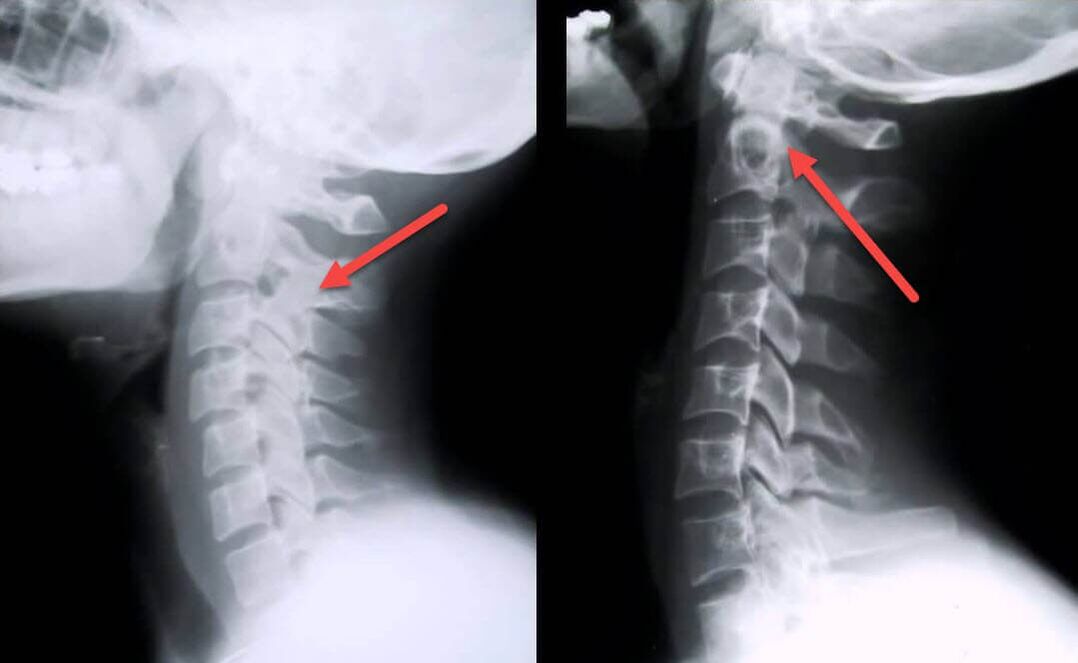

Das aussagekräftigste diagnostische Verfahren ist das Röntgen. Pathologien 1. Grades entsprechen dem 1. oder 2. radiologischen Stadium. Die resultierenden Bilder zeigen typische Anzeichen der Krankheit.

| Radiologische Stadien der zervikalen Osteochondrose ersten Grades. | Charakteristische Zeichen |

|---|---|

| Stufe 1 | Kleinere Veränderungen der Krümmung der Wirbelsäule im Halsbereich, die ein oder mehrere Segmente betreffen. |

| Stufe 2 | Leichte Verdickung der Bandscheiben, Verformung der Processus uncinatus, Aufrichtung der Lordose, geringfügige Wucherungen der Knochenstrukturen. |